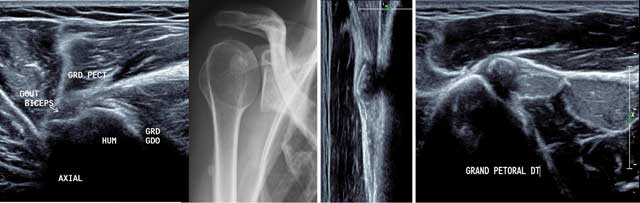

Figure 17

Axial view of the distal and lateral part of the deltoid muscle. CA: Anterior chief, CM: Medium chief, CP: Posterior chief.

Figure 18

Axial view of a recent traumatic extrinsic lesion of the medium chief of the deltoid with hyperhemia (a–c).